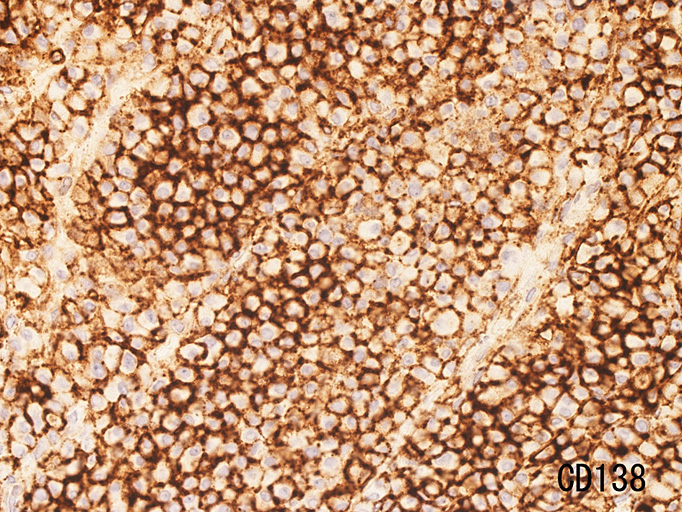

鼻腔内腫瘤生検組織 病理所見

免疫染色

plasmacytoma